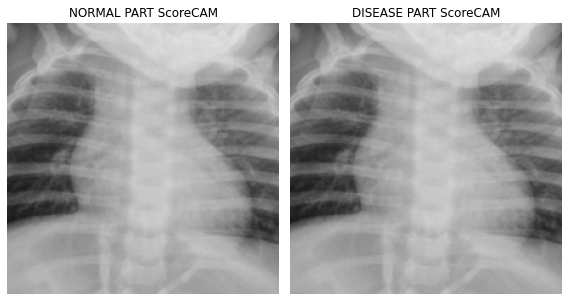

fig, (ax1,ax2) = plt.subplots(1,2)

dls.train.decode((x,))[0].squeeze().show(ax=ax1)

ax1.imshow(-cam_scorecam.squeeze(),alpha=0.5,extent=(0,224,224,0),interpolation='bilinear',cmap='cool')

ax1.set_title("NORMAL PART ScoreCAM")

#

dls.train.decode((x,))[0].squeeze().show(ax=ax2)

ax2.imshow(cam_scorecam.squeeze(),alpha=0.5,extent=(0,224,224,0),interpolation='bilinear',cmap='cool')

ax2.set_title("DISEASE PART ScoreCAM")

fig.set_figwidth(8)

fig.set_figheight(8)

fig.tight_layout()